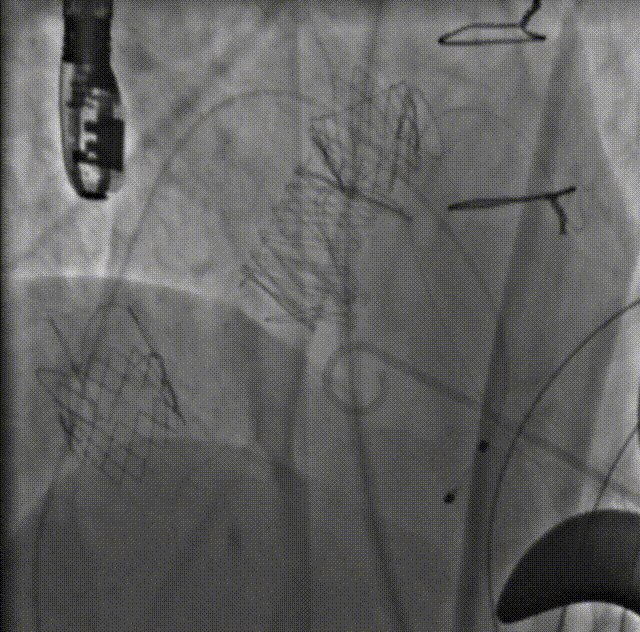

球囊后扩

二尖瓣入位

主瓣造影

左室造影